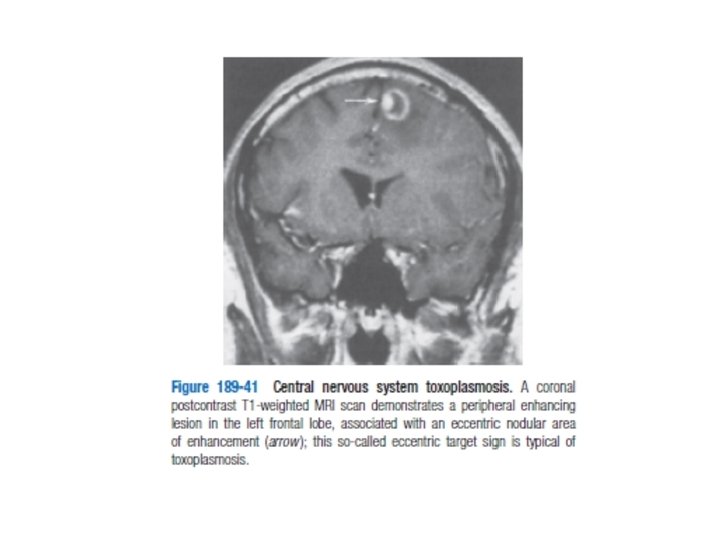

NÖROLOJİK KOMP. Toksoplazmosiz; • En sık fokal ensefalit nedeni – Ateş, baş ağrısı, nörolojik defisit, nöbet • BOS’ta T. Gondi antikor (düşük spesifite) • BT&MRG ile bazal ganglion lezyonları – Ayrıcı tanı; lenfoma, tbc, fungal enfeksiyon • Hospitalize tedavi ve ileri inceleme gerekir – Falinik asit+primethamin ve sülfadiazin tdv.